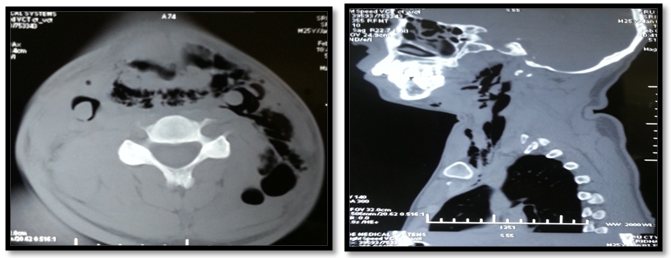

Traumatic airway injuries are fortunately rare. Though injuries can be obvious and initial management straightforward, the diagnosis can be difficult. Laryngeal trauma could either be a blunt trauma or a penetrating injury. It has been reported in US that less than 1 percent of all trauma involves the larynx.7 In the United States, the incidence of both forms of injury in the 1980s ranged from one in 5,000 emergency visits8 and one in 30,000 emergency visits in the 1990s.5 Concurrent injury to the pharynx and/or esophagus is infrequent in both penetrating and blunt laryngeal trauma.9 The most common finding in these patients has been dysphonia and pain/tenderness of the larynx.5 CT imaging is beneficial in patients with a significant history of blunt force trauma to the anterior neck with or without significant abnormal findings on physical examination, particularly with dysphonia or hemoptysis, and if the condition and continuity of the endolarynx and trachea is not observable due to edema or hematoma.3 Video stroboscopic laryngoscopy provides an excellent assessment of vocal fold mobility and integrity, and potential reversibility of injuries.10 Stroboscopic examination is also useful for the assessment of recovery. The timing of early surgical management ranges from within 24hours to several days. However it has been reported by Herbert Harris in 1965 and 1970 that surgery is beneficial within 24hours of injury11,12 Following acute airway management, laryngeal injuries are managed based on the severity of injury and specific elements of each lesion. A classification and treatment protocol has been described by Schaefer5 Group I laryngeal traumas demonstrate only minor laryngeal edema or lacerations. Typically, this group can be treated with steroids, antibiotics, antireflux therapy, close observation. Group II includes more demonstrative edema or hematomas without exposed cartilage. Diagnostic endoscopy and tracheostomy are frequently indicated for this group. Group III laryngeal traumas demonstrate massive edema or large mucosal lacerations. Conservative management includes anti inflammatory, anti relux, antibiotics and corticosteroids. Surgical management includes tracheostomy, direct laryngoscopy and oesophagoscopy open operative interventions and laryngeal stents (Figures 3-7).

Figure 4 Fracture of thyroid cartilage at the midline with mild lateral displacement of the right side ala.

Figure 6ballooned up arytenoids and displacement fragment of thyroid cartilage.

Figure 7CT- Neck showed extensive subcutaneous emphysema with extension into posterior pharyngeal space and left posterior neck space.